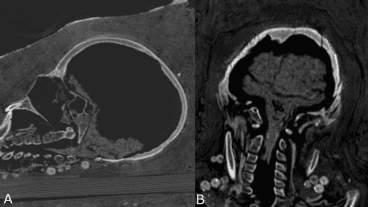

Mediante análisis de tomografía computerizada, los investigadores lograron obtener información sobre el estado de conservación de los cuerpos, la técnica de momificación artificial usada, la edad de los individuos en el momento de la muerte, así como su género, altura y salud.

"Las investigaciones radiológicas anteriores de las momias de los períodos romanos ya revelaron que algunas no mostraban evidencia de extirpación del cerebro y de los intestinos. La identificación del cerebro conservado en el caso de la mujer joven apoya, por lo tanto, esta idea", explicó a IFLScience, el investigador principal del estudio, Stephanie Zesch.

Este nuevo tratamiento fue posible identificarlo solo en la momia joven, pues los cuerpos del hombre y la otra mujer estaban "bastante mal conservados" y no se pudo determinar una técnica específica de momificación artificial.